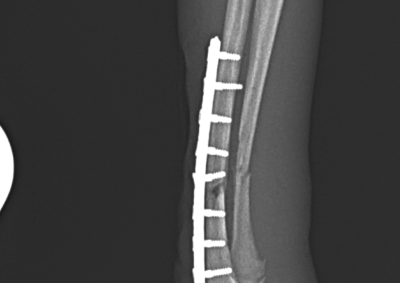

整形外科 注意 ボタンをクリックした先に、治療中および手術中の画像が説明で使用されている場合がございます。 そのような画像に弱い方は閲覧なさらないようお願いいたします。 整形外科 股関節脱臼に対する大腿骨頭頸部切除術 整形外科 橈骨固定術(骨端板骨折)#246 整形外科 膝蓋骨内方脱臼に対する人工滑車置換術 #19 整形外科 CBLO #238 整形外科 膝蓋骨内方脱臼 G4に対するPGR#18 整形外科 橈骨固定術 #245 整形外科 猫の脛骨骨折〜シャイな子を救う、やさしい手術〜 整形外科 三点骨盤骨切り術(Triple Pelvic Osteotomy) 整形外科 レッグ・ペルテス病に対するFHNE 整形外科 膝蓋骨内方脱臼G3に対するPGR#17 整形外科 猫の足根中足関節脱臼 整形外科 MPL G4に対するPGR #15+TTT <«345678910111213> 症例カテゴリー 放射線治療整形外科軟部組織外科脳神経外科内科腫瘍外科救急・集中治療リハビリテーション科腫瘍内科内視鏡科脳神経科呼吸器外科中医・漢方猫の腎移植循環器科